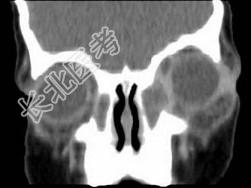

- 多项选择题女,2岁, 左侧眼睑肿胀发热,CT检查如图所示, 正确的描述或诊断是 ( )

A、左侧鼻骨外侧旁见软组织块影

B、其内密度不均,可见低密度影

C、左侧鼻泪管囊肿

D、鼻泪管脓肿

E、混合瘤